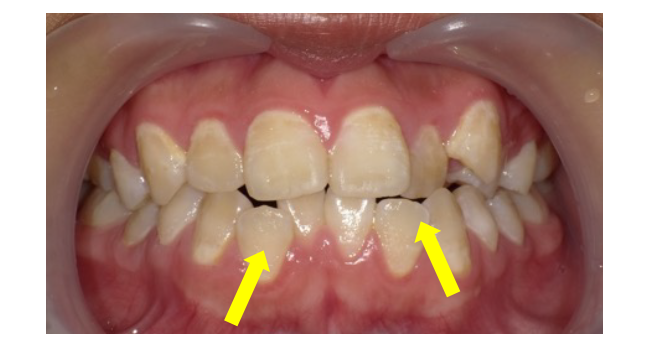

(相談症例 ケース No.501)

生年月日 〇〇年1月24日 11歳4か月 女性(作成日 令和〇〇年6月19日)

(症状、患者さんの主訴について)

① 左側上下顎前歯が反対になっている。

② 右下前歯が、前に出ている

③ 顎前歯が、重なっている。

④ 話の時、発音が悪い時がある。

△△歯科で、小学2年生頃に歯並び相談をしたところ、「様子見ましょう。」と言われました。

| 親戚に反対咬合の患者さんの有無 | 母親 反対咬合 |

| 態癖 :顎の発育に影響します。 気が付いた時には、「仰向け」に直しましょう。 |

あり 左下寝 左頬杖 睡眠時間は、8~9時間 就寝時の「歯ぎしり」→顎が狭いと、「歯ぎしり」をする場合があります。 |